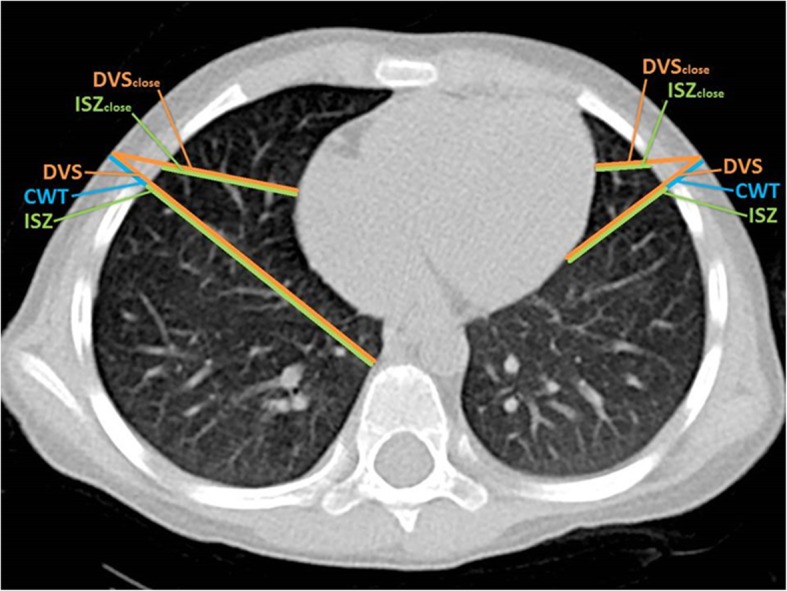

Measurements were made at 2nd ICS MCL and 4th ICS AAL on both sides of the thorax. ICS width was measured from the inferior border of the superior rib to the superior edge of the inferior rib. Chest wall thickness and the depth to the closest vital structure were measured in various directions: in the sagittal plane at the 2nd ICS MCL (MCLsag), perpendicular to the chest wall at the 2nd and 4th ICS (MCL perp, AAL perp) and in a linear direction to the closest vital structure at the 2nd and 4th ICS (CWTclose) (Fig. 1, Table 2) Intrathoracic structures classified as “vital structures” are shown in Table 3. Lung parenchyma was not classified as a vital structure. Since a pneumothorax in the prehospital setting can hardly be confirmed with a 100% accuracy and an accidental puncture of the lung parenchyma is possible, we chose to define the intraparenchymal lung vessels up to the segmental vessels as vital structures. Chest wall thickness was measured from the skin surface to the pleural cavity. Depth to vital structure was defined as the distance from the skin surface to the intersection with a vital structure. In an additional measurement, the closest vital structure to skin surface at the insertion sites was identified visually. The distance from skin surface to this reference point at the corresponding puncture site was measured. The distance for the worst case scenario; an insertion leading directly to the closest vital structure, was determined (DVSclose). By subtracting CWT from DVS, the so called “intrapleural safety zone (ISZ)” was calculated. ISZ represents the intrathoracic distance from entering the pleural space up to the beginning of the closest vital structure (Fig. 1).

Fig. 1.

Graphical display of measurements taken. 4th ICS AAL. DVS: depth to vital structure, CWT: chest wall thickness, ISZ: intrapleural safety zone. Subscript “close” indicating measurements for a misguided puncture directed at the closest vital structure